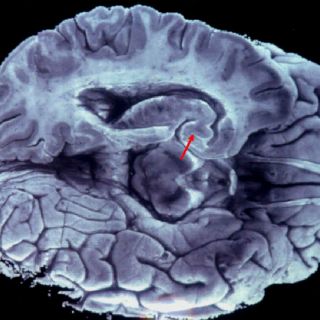

Pudiera tratarse de una falla entre el lóbulo frontal y la corteza cerebral

CIUDAD DE MÉXICO (17/MAR/2016).- Las alucinaciones auditivas y visuales son más frecuentes de lo que pudiera pensarse, y para que ocurran no se necesita algún tipo de sustancia, sino una falla entre el lóbulo frontal y la

corteza cerebral.

John McGrath, especialista del Queensland Brain Institute, señaló que en ocasiones algo va mal en la relación lóbulo frontal-corteza cerebral, y se genera la falla de percepción o alucinación, publicó la Australian Broadcasting Corporation (ABC).

Puntualizó que cuando todo va bien, el lóbulo frontal está al mando y controla al conjunto del cerebro, pero situaciones como las señaladas, reducen su eficiencia y es cuando se puede crear la alucinación.